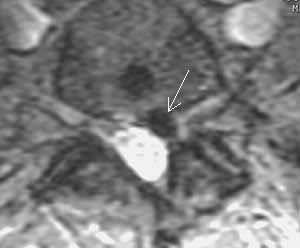

Рис 2. Обызвествленная пролабированная часть диска L5-S1 в правом латеральном кармане. (Слева) Имеет пониженную интенсивность при GRE  последовательности (стрелка). (Справа) Обызвествление хорошо видно на КТ.